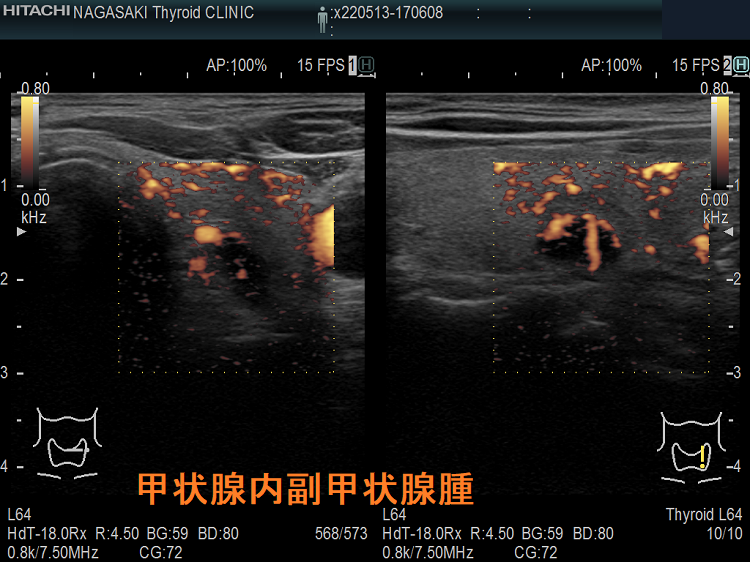

甲状腺内副甲状腺腫は、原発性副甲状腺機能亢進症の1.4 ~ 2.1%を占めます[Surgery. 2009 Dec;146(6):1144-55.]。

甲状腺内副甲状腺腫は、超音波(エコー)検査で甲状腺腫瘍と形態的に鑑別できない場合があります(実際は下の写真のように診断できていますが・・)。特徴的な超音波(エコー)所見は、腹側の高エコーで感度86%、特異度100%です[Surgery. 2012 Dec;152(6):1193-200.]。さらに、99m-Tc MIBIシンチグラフィーで取り込み(集積)があれば甲状腺内副甲状腺腫と診断できます。

99m-Tc MIBIを取り込まない甲状腺内副甲状腺腫もあるため、穿刺細胞診を行い、針先洗浄液でインタクトPTHを測定(FNA-PTH)。甲状腺内副甲状腺腫は、甲状腺が周囲にあるため、針に沿った副甲状腺細胞のばらまき(播種)・出血の危険が少なくなります。

腺腫様甲状腺腫に合併する甲状腺内副甲状腺腫

腺腫様甲状腺腫に合併する甲状腺内副甲状腺腫は、腺腫様結節と鑑別が難しいだけでなく、多腺性(5-6腺)のケースがあります。